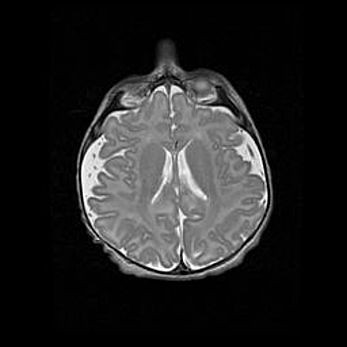

Множественные кисты обоих полушарий головного мозга, наибольшая из них в правой затылочной области. Ассиметричная атрофическая гидроцефалия.

Возраст: 7 месяцев

Вес: 5660 г

Пол: мужской

Окружность головы: 41,5 см

Срок гестации: 28-29 недель

Кисты головного мозга развиваются в результате многоочаговых некрозов вещества мозга и возникают вследствие перенесенной перинатальной инфекции, менингитов, энцефалитов, асфиксии, родовой травмы, расстройств мозгового кровообращения различного генеза. Образованию кист в веществе головного мозга плодов и новорожденных способствуют такие факторы, как высокое содержание в нем воды, недостаточная (или отсутствие) миелинизация и слабая астроглиальная реакция на повреждение.

Кисты могут сочетаться с гидроцефалией и другими поражениями головного мозга.